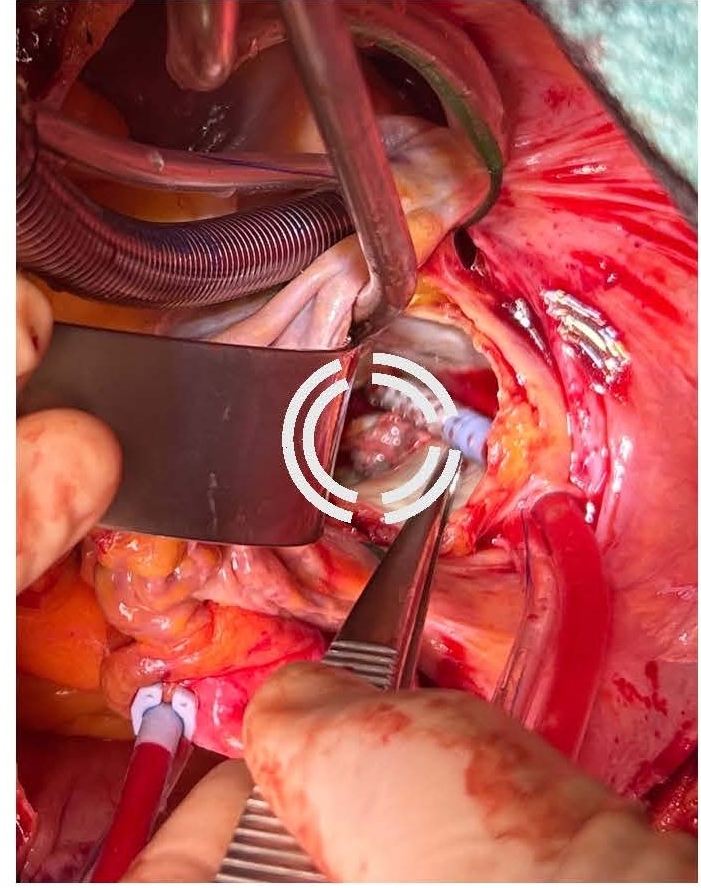

Given the severe clinical presentation, a decision was made to proceed with urgent cardiothoracic surgery on post-ablation day 26. Left atriotomy revealed a substantial vegetation associated with a necrotic fistulous orifice of approximately 1.5 cm in diameter located on the posterior wall of the left atrium near the left pulmonary vein ostia (Figures 5 and 6). The vegetation was resected, and purulent secretions were expressed from the fistulous orifice. Cultures of these samples later showed contamination with Staphylococcus aureus and Streptococcus anginosus. The fistulous orifice was closed using an autologous pericardial patch (Figure 7).

Figure 5. Mass in the posterior wall of LA.

Figure 6. Fistula visible on the posterior wall of LA.